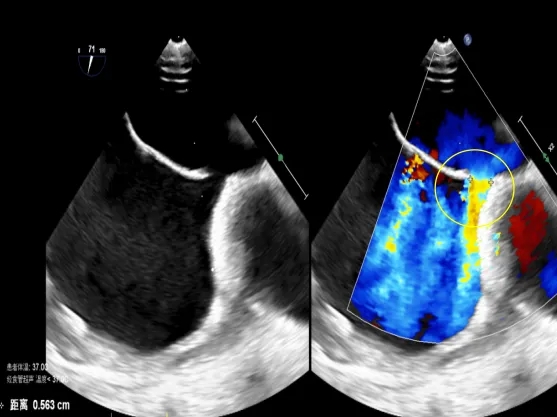

经食道超声可见

第二个缺损5.63mm

术中超声:术中经食道超声可见有两个缺损,分别为8.06mm、5.63mm,和术前超声报告对比有所偏差,两缺损距离约8.48mm。